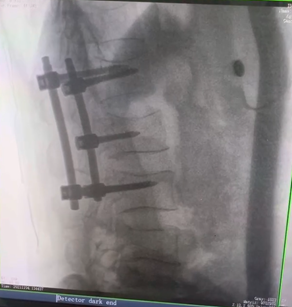

例如治療先天性脊柱側(cè)后凸畸形,由于脊柱自身復(fù)雜的解剖結(jié)構(gòu)限制,使得脊柱外科手術(shù)對于精確度有著較高要求。以往我們只能采用傳統(tǒng)的正側(cè)位圖像來判斷螺釘置入的位置,現(xiàn)在三維C形臂特有的類CT斷層成像,使得治療過程可視化,立體化,在術(shù)中非常直觀地判斷螺釘植入的準確度??捎行б龑?dǎo)術(shù)者植入后路螺釘并切除半錐體。同時可以在術(shù)中實時驗證手術(shù)效果。有效地縮短了手術(shù)時間,降低手術(shù)風險,避免了不必要的術(shù)后翻修手術(shù)。

另外,三維C形臂采用12英寸(30cm x 30cm)的平板探測器,成像區(qū)域大,有效成像面積比9英寸傳統(tǒng)影增提升了100%,可一次拍七節(jié)頸椎、五節(jié)腰椎、十二節(jié)胸椎、雙側(cè)骶髂關(guān)節(jié)、股骨頭及單側(cè)盆骨。